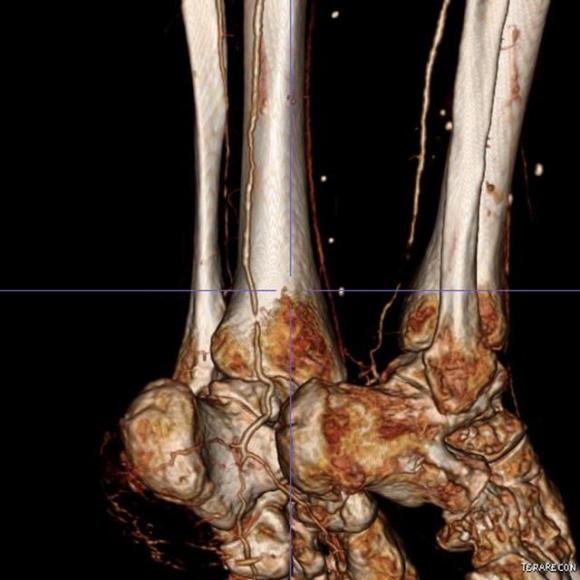

The patient is a gentleman from out of state who had called about problems he was having with walking and with leg ulcers that wouldn’t heal. He is in his seventies and has a pacemaker for an arrhythmia for which he was on Xarelto. He also had type II diabetes. He had bilateral lower extremity deep venous thromboses 6 years prior requiring IVC filter placement. The filter occluded, and it resulted in sudden sharp and debilitating pain in both legs with walking short distances -some days only 50 paces.He described it as an unbearable pain in calves and thighs that felt like his legs were going to burst. He also had ulcers on his legs that would heal with ministration but soon recur. This was all despite being quite active, with regular workouts, and being fit. He was compliant with compression. He sent a CT scan done last year (below).

It showed an Optease retrievable vena cava filter that was occluded and the iliac systems bilaterally (right above and left below) were chronically occluded with patent vena cava above and femoral confluences bilaterally below.

Examination revealed a fit and trim man in his 70’s in no apparent distress. He had bilateral leg edema that was moderate with small superficial and tender ulcers of the right posterior distal calf. Pulses were normal. He was taken to our hybrid suite and venography from femoral vein access in the proximal thigh in the supine position revealed his right and left iliac venous systems to be occluded (below figures).